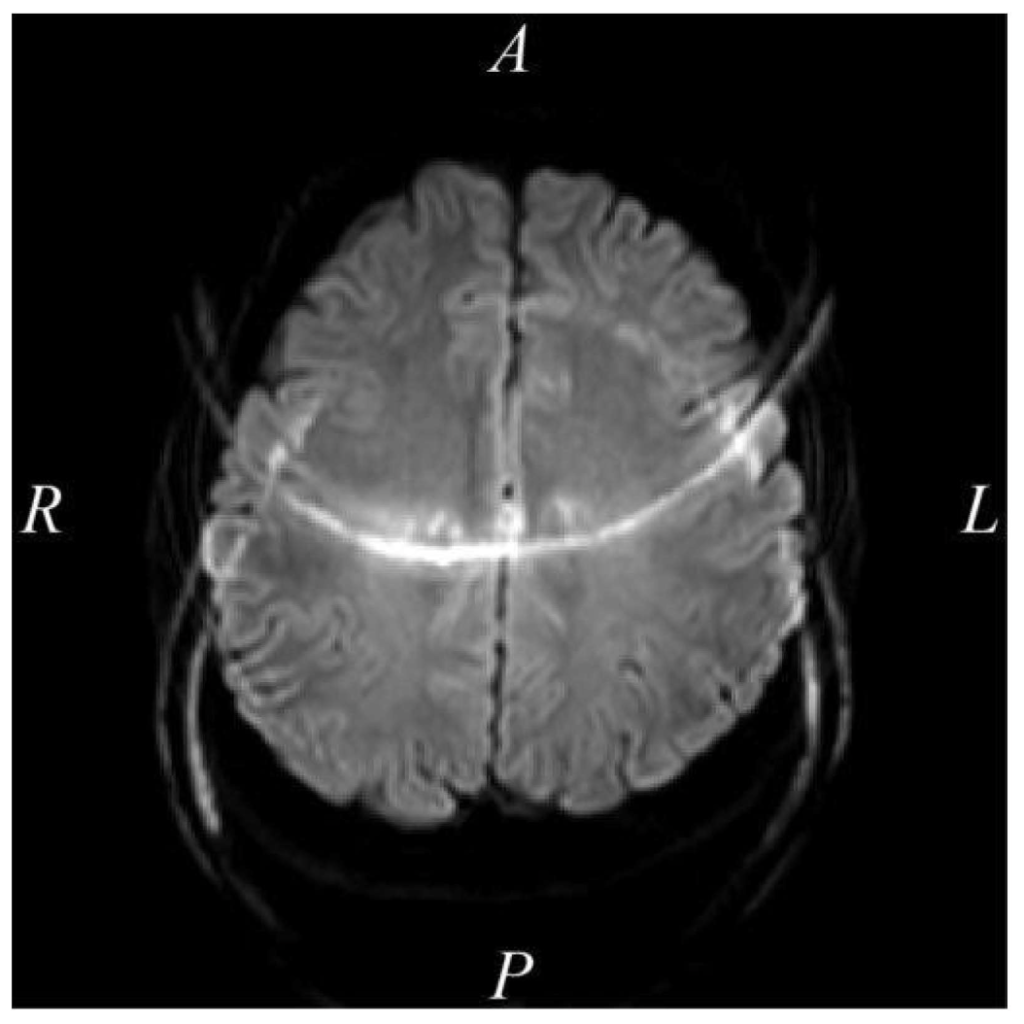

問題 18 シングルショットEPI法で得られた拡散強調画像を示す。このアーチファクトについて正しいのはどれか。2つ選べ。

1. ADC値は不正確になる。

2. 周波数エンコード数は関与しない。

3. 位相エンコード方向はRL方向である。

4. 原因は偶数番目と奇数番目のエコー間の位相シフトである。

5. 発生位置はパラレルイメージングの倍速ファクタで変化する。